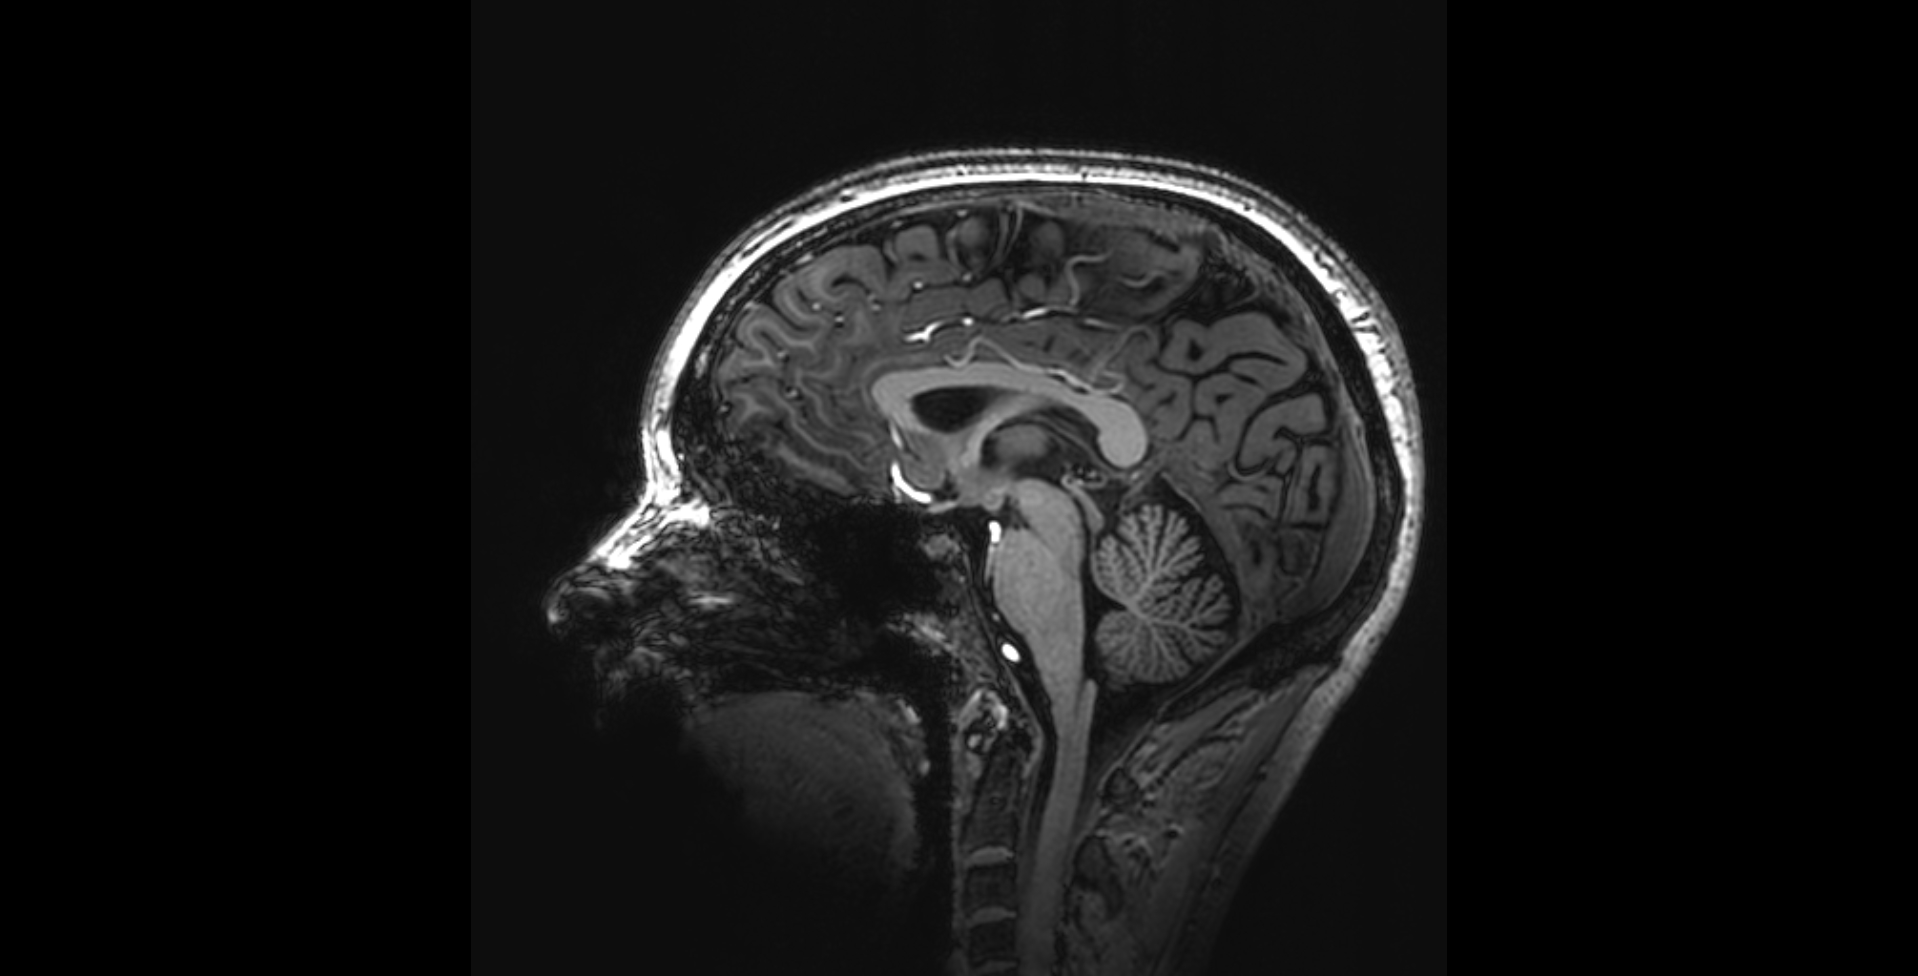

Dementia is a devastating neurodegenerative disease that has great impact into the daily lives of people with dementia and their caregivers.

My research focuses on improving dementia diagnostics and postdiagnostic care by attending to specific needs and characteristics of individuals. I improve person centered care, by accounting for to the fact that every person is different. I focus for example on improving the care for young onset dementia patients, culture sensitive care, and early recognition and person centered interventions for neuropsychiatric symptoms in Alzheimer's disease.

• 2009-2012 PhD project 'Functional neuroimaging in dementia'